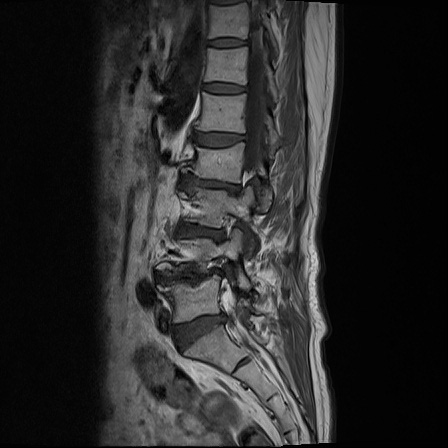

Ӵϲ ɿ ô ô 㸮 ٸ ̾ϴ. ϵ Ͻð ܻ 㸮 20⵿ ͽϴ. mri ˻ ɿ Ȳ ʹ ؼ Ȳ̶ ߽ϴ. ϻȰ ϰ 鼭 ½ϴ. ̴ ø鼭 Ͻô Ȳ ̷ ġ ص ȸ ϴ. δ Ҵµ, ù ȸԲ ˷ֽ ϰ β ϰ, ˷ֽ ü ƮĪ ϸ鼭 ȭǸ鼭 Ӵϲ ȸų ְ ǰ, β 鼭 ʴ β ؾϴ ŷο 1ϸ ijħ ڸ ǥ Ʈ ߽ϴ. ȸ ȭϽø鼭 Ϸ簡 ٸ ȸǽð 4ְ Ǿ Ǯ鼭 ¦ ҽϴ. ħ ȸ ȭϸ鼭 ڼ ü ƮĪ ϴ. ȥڼ Ͻʴϴ. ٳø鼭 ó Ͻ ʴϴ. ̾ ְ ̳ ߵ ʰ ϴ ȸԲ Ͻʴϴ. ʹ ϸ鼭 ϴ. Ȩ - ϱ ٴ Ȳ MRIԴϴ. |